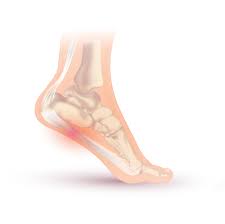

전형적인 증상은 아침에 일어나 처음 발을 디딜 때 느껴지는 심한 통증이 특징적이지만, 모두 같은 증상을 겪는 것은 아니다. 통증은 주로 발꿈치 안쪽에 발생하는 경우가 대부분이고 발뒤꿈치뼈 전내측 종골 결절 부위를 누르면 통증이 발생하기도 한다. 발가락을 발등 쪽으로 구부리면 통증이 심해지기도 한다.

주로 가만히 있을 때는 통증이 없다가 움직이기 시작하면 통증이 발생하고 일정 시간 움직이면 통증이 다시 줄어드는 양상이 많다. 진행된 족저근막염의 경우에는 서 있을 때 뻣뻣한 느낌이 지속되고 하루 일과가 끝나는 시간이 가까울수록 통증의 정도도 심해지는 경우가 있다.